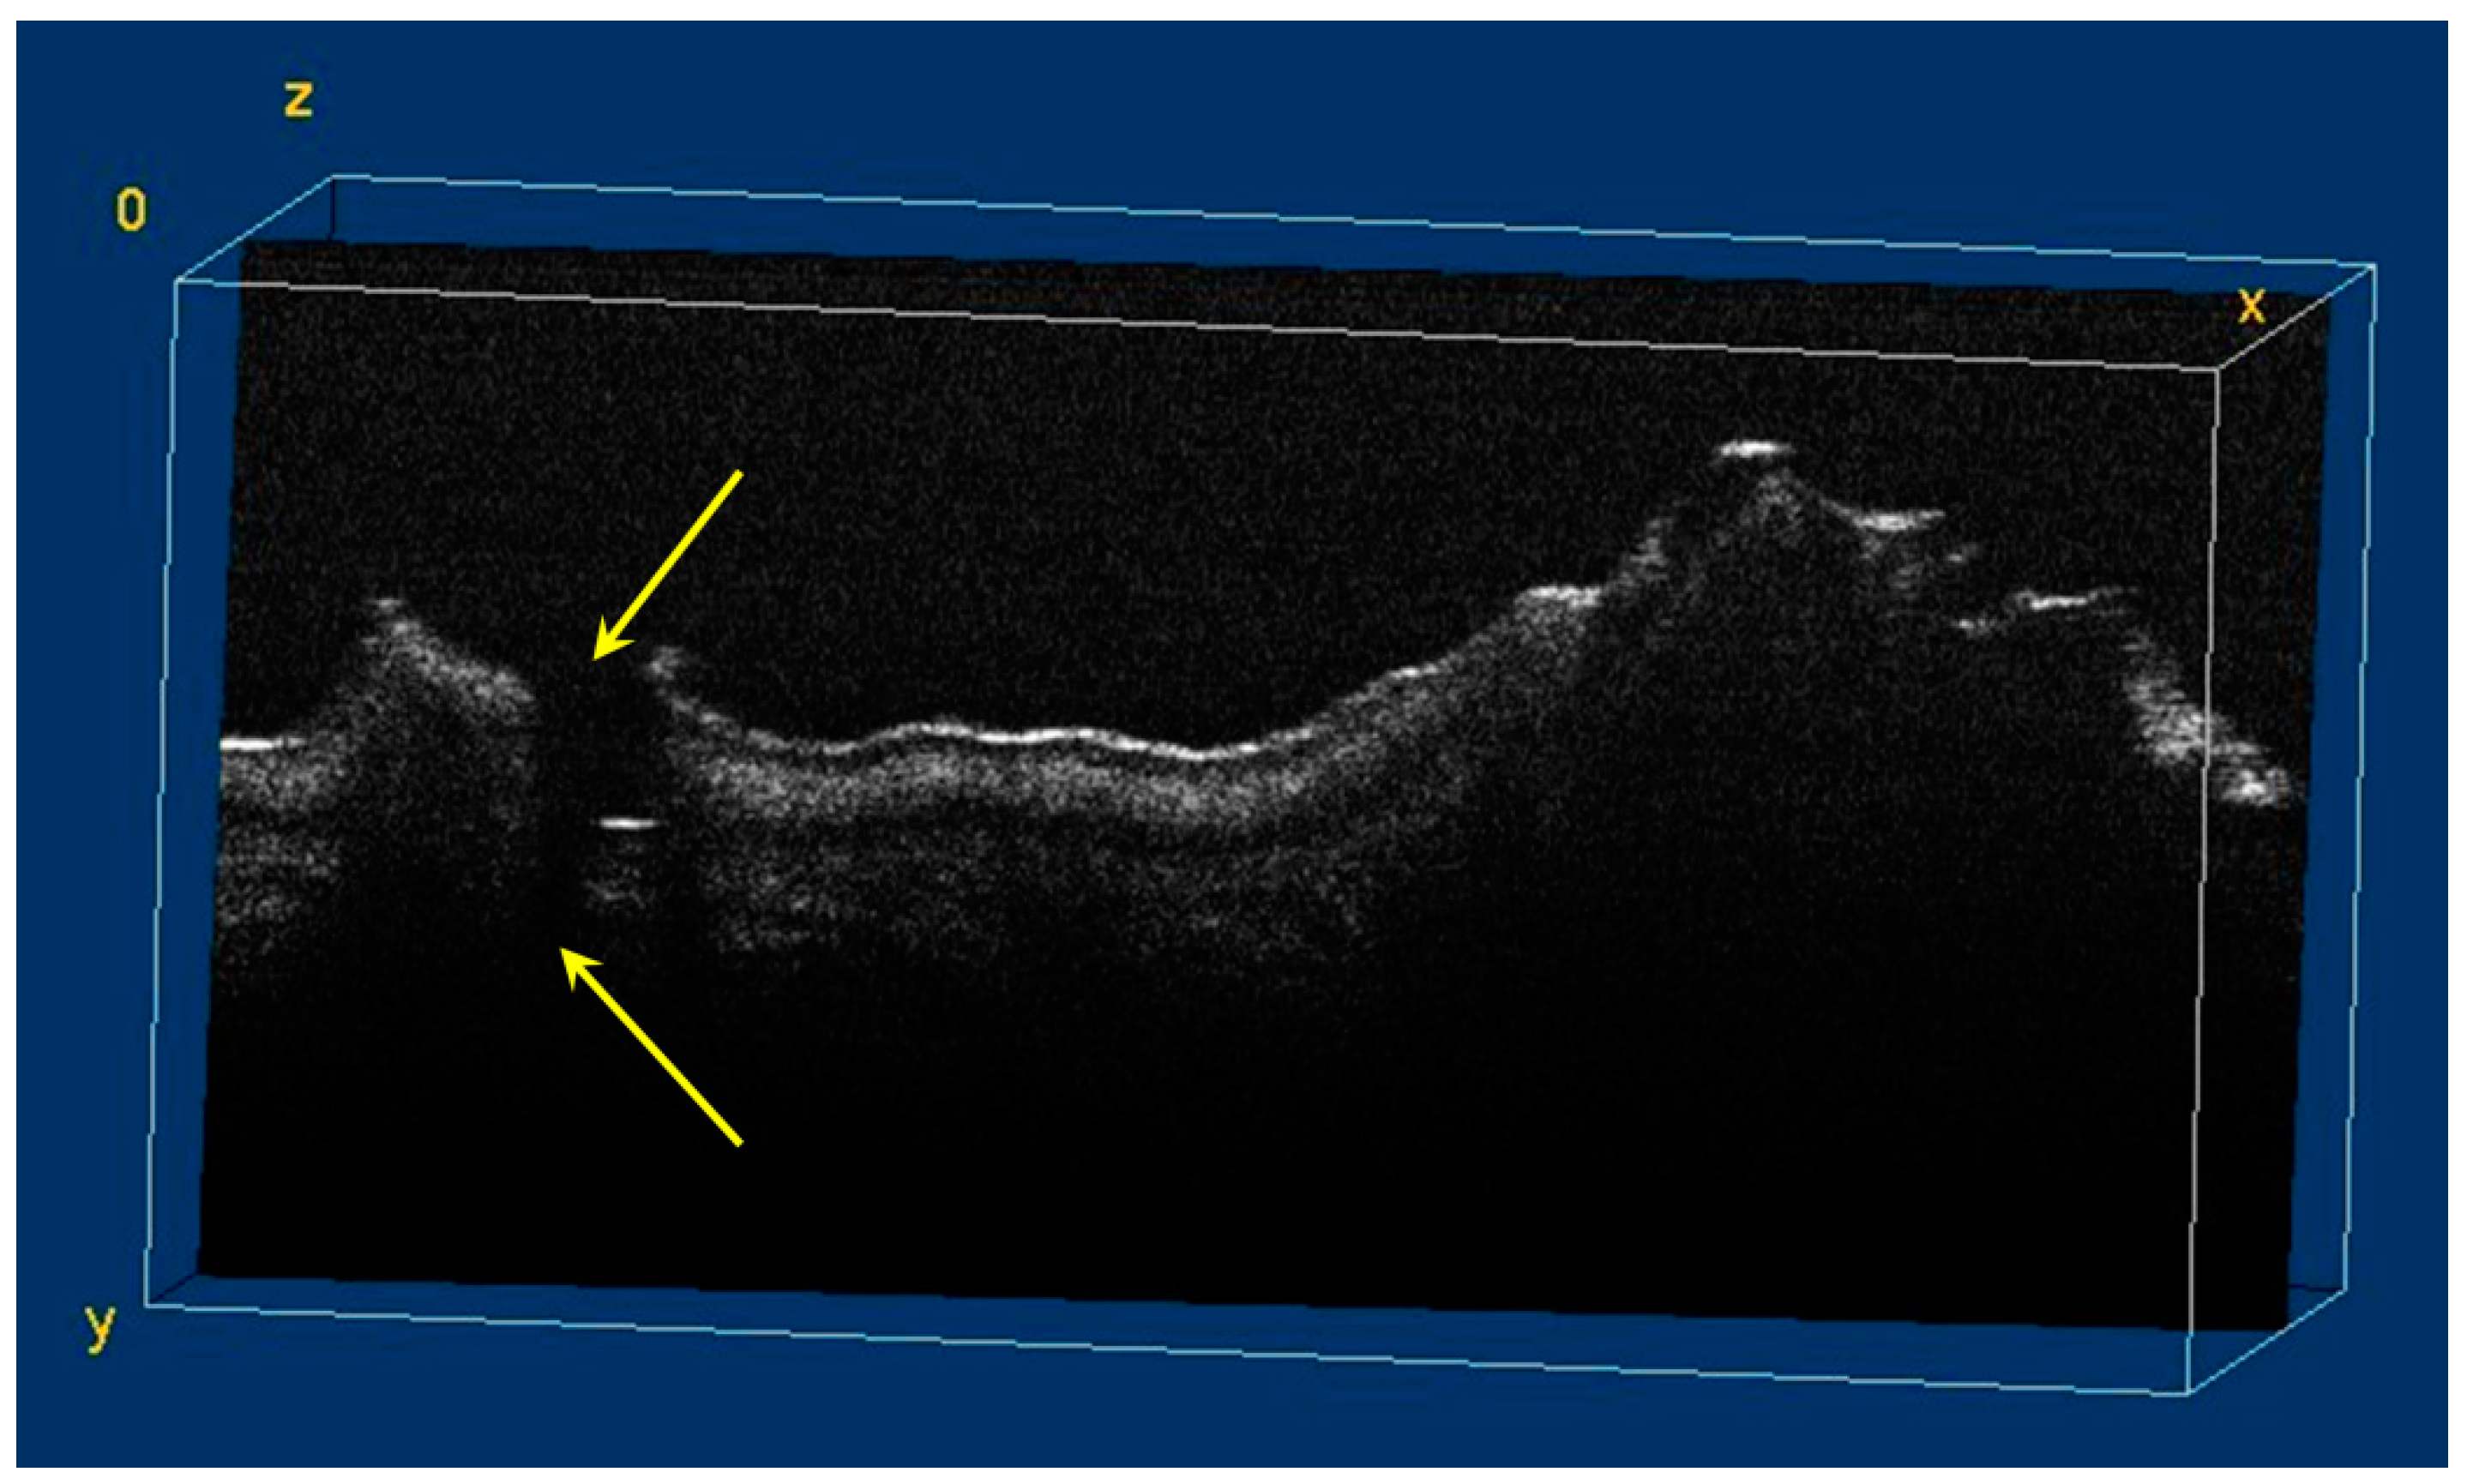

The image processing using ImageJ software showed the spatial disposition and extent of the hypomineralization lesions and hypoplasia (Figure 6, Figure 7, Figure 8 and Figure 9).

Figure 7.

Volumetric reconstruction (in ImageJ) of hypomineralization areas marked by blue arrows. The yellow arrow indicates a small hypoplasia lesion, which was not initially identified in 2D OCT images analysis.